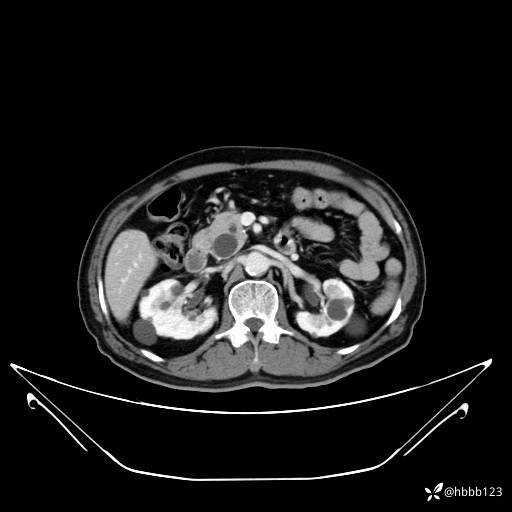

动脉期: